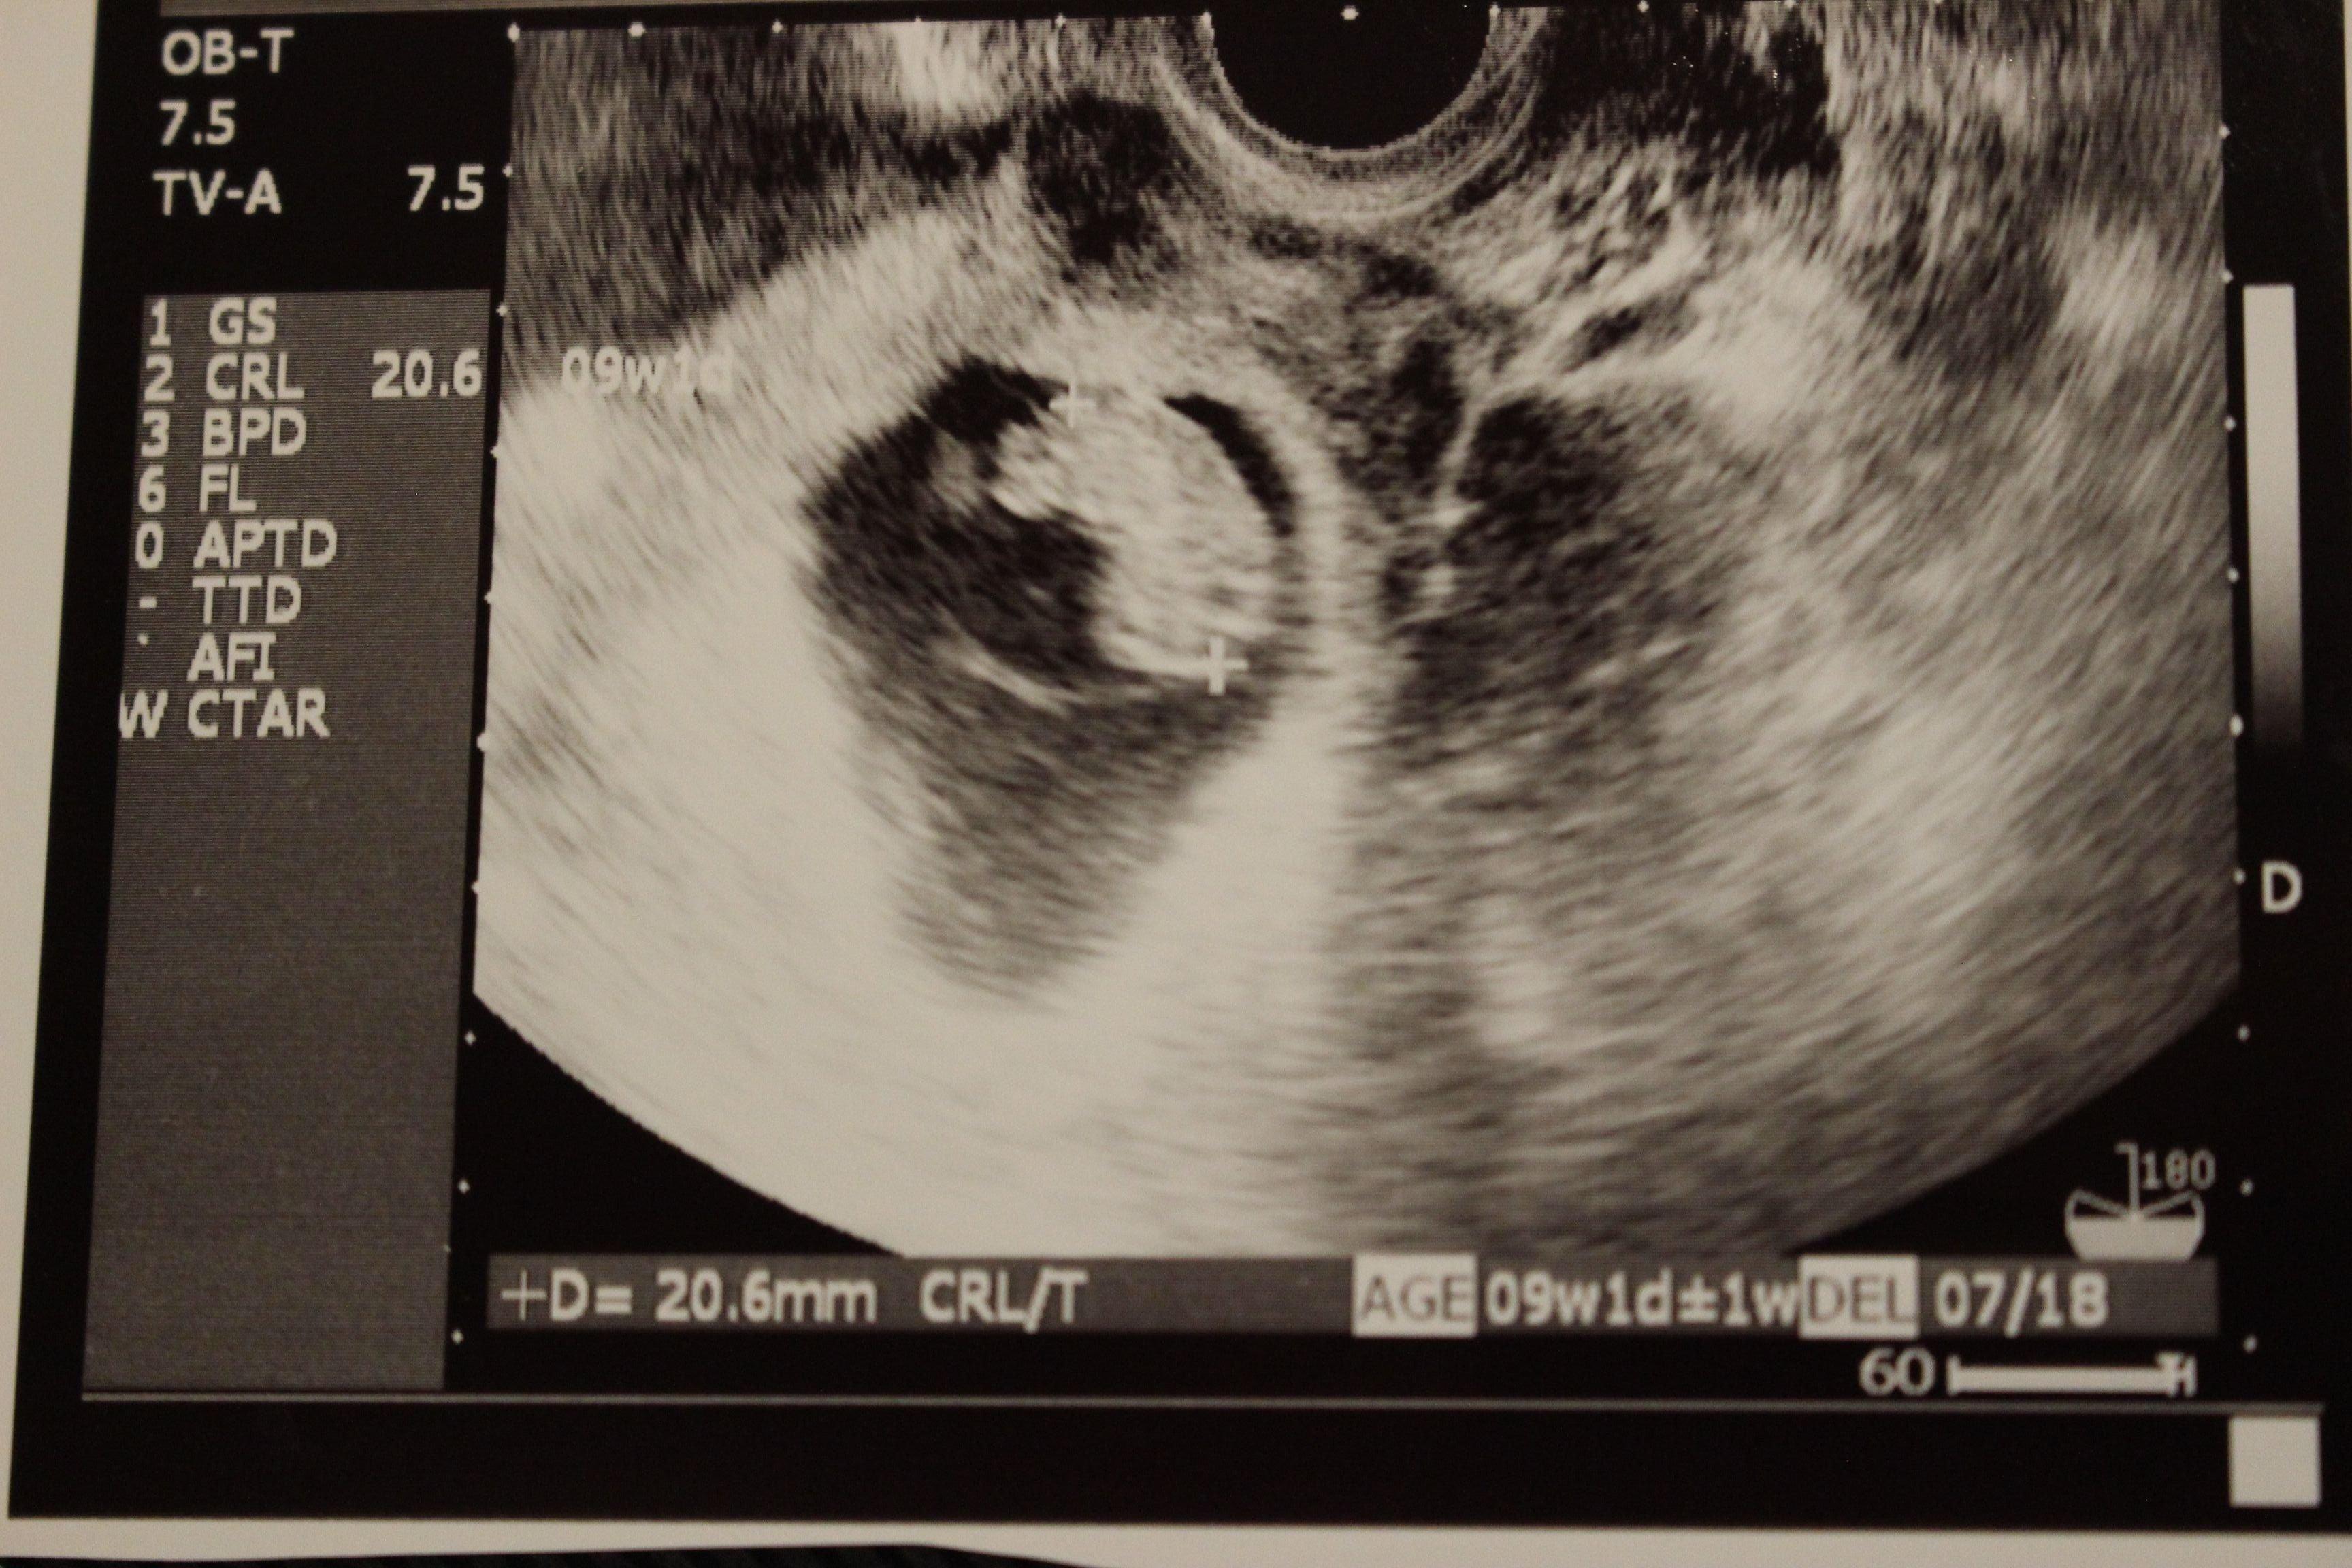

妊娠9週目のエコー写真

何となく頭と胴体の区別が出始め、胎芽から胎児とよばれるようになりました。スリムな人だとまだおなかの膨らみが分からない頃ですが、嬉しくてウエストノーマークのマタニティ服を着て過ごしていました。